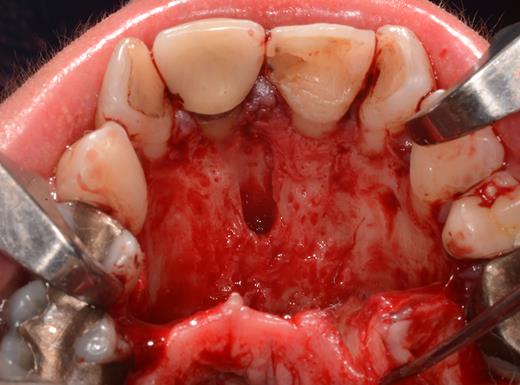

After a sulcular incision on the palatal side from teeth 15 to 25 and an incision in the midline of the palate omitting the incisive papilla and the two orifices of the NPD, two full-thickness mucoperiosteal flaps were raised. Thereafter, the incisive papilla and the whole contents of the incisive canal were enucleated (Figs 4–6). The bony incisive canal was filled with autologous bone harvested from the palatal region (bone scraper) (Fig. 7). A tension-free primary wound closure was achieved by moving the palatal flaps to the midline using single button and interdental vertical mattress sutures (Monocryl 4-0, Ethicon, Johnson & Johnson, USA) (Fig. 8). To avoid wound dehiscence and hematoma, an iodoforme gauze and a palatal plate were applied (Fig. 9). The patient was instructed to rinse three times a day with 0.1% chlorhexidine (formula hospitalis) for 2 weeks postoperatively. Sutures were removed after 14 days.

Excised soft tissue contents of the incisive canal including the neurovascular bundle and the incisive papilla.